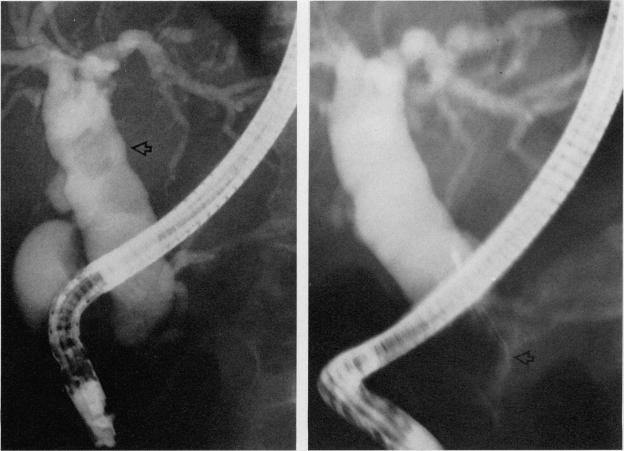

Endoscopic sphincterotomy was performed in 22 patients with biliary obstruction. Nineteen patients had obstructing choledocholithiasis and three patients had distal common-bileduct obstruction due to malignant disease. All patients had excellent biliary decompression. Three patients had complications that responded to medical management. Endoscopic sphincterotomy is a safe and effective procedure for the nonsurgical management of obstructive-biliary-tract disease.

对22例胆道梗阻患者实施了内镜括约肌切开术。19例患者患有阻塞性胆总管结石,3例患者因恶性疾病导致胆总管远端梗阻。所有患者的胆道减压效果均良好。3例患者出现了经药物治疗有效的并发症。内镜括约肌切开术是一种用于非手术治疗阻塞性胆道疾病的安全有效的方法。